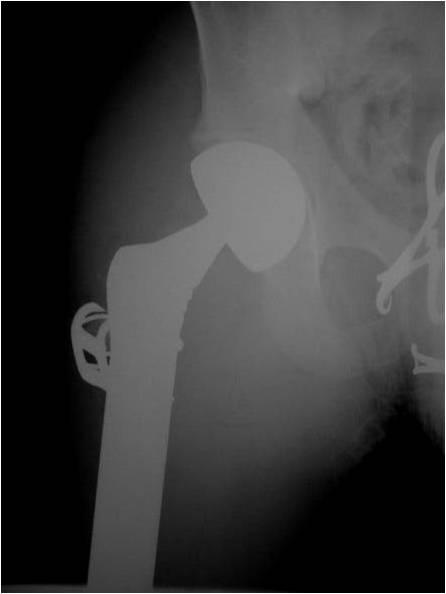

- Most protocols administer preoperative chemotherapy then surgery is performed. Surgery is followed by several courses of postoperative chemotherapy.

- Ewing sarcoma responds well to chemotherapy. Often there is a dramatic reduction in size of the tumor.

- Most common chemotherapy agents utilized include as of 2008: Vincristine, Adriamycin, Cyclophosphamide, Actinomycin-D, Ifosfamide, Etoposide

- Surgical resection

- Limb sparing surgery whenever feasible unless there will be a large leg length discrepancy that can not be accomodated for with surgery

- Rarely ever an amputation since Ewing sarcoma are sensitive to radiation

If surgical resection is not feasible, radiation may be utilized for local control (instead of an amputation) since Ewing sarcoma is highly sensitive to radiation, at least as per the author’s opinion. There may be some tumors that are selectively treated with radiation instead of surgery however most patients as of 2008 are treated with limb sparing surgery whenever feasible. Sometimes radiation is used in conjunction with surgery if a wide margin was not obtained at the time of surgery. The decision to administer radiation depends on size of tumor, site of tumor, response of tumor to preoperative chemotherapy and risks vs benefits of radiation.